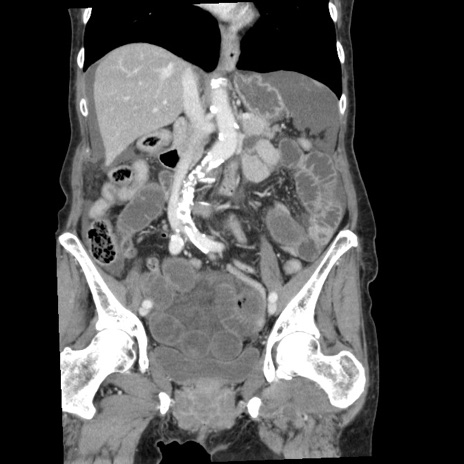

症例1(冠状断像)

【症例】80歳代女性

【主訴】腹痛

【現病歴】8時間前から腹痛あり来院。

【既往歴】糖尿病、脂質異常症、子宮体癌にて子宮全摘術

【身体所見】意識清明・会話良好だが腹痛で苦悶様、全腹部にわたって反跳痛と圧痛あり

【データ】WBC 13600、CRP 0.14、LDH 224、CK 90